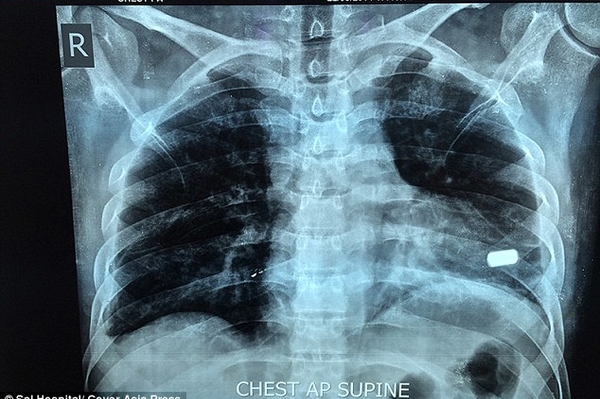

32-летний индиец Бхарат Шарма из города Алигарх, что в штате Уттар-Прадеш, Северная Индия, два месяца прожил с пулей в сердце. 22 июля мужчина стал случайным свидетелем ограбления банка, за что и пострадал. Один из грабителей открыл огонь, в результате чего в Бхарата попало две пули. Одна из них угодила в левый бок индийца и не задела жизненно важных органов, другая же попала прямо в сердце.

Из тела чудом выжившего мужчины одну пулю извлекли только через неделю после нападения, а другую, опасаясь за его жизнь, удалять отказались.

Доктор Анил Джейн, кардиохирург, который руководил операцией, сказал, что это был очень редкий случай, и удивительно, что пациент жил с пулей в сердце в течение двух месяцев: "Пуля находилась в сердечной мышце у верхушки левого желудочка, одной из двух камер сердца. Это уникальный случай, который запросто мог стать фатальным. То, что он прожил два месяца с пулей в таком месте - уникальный случай, это очень счастливый человек"

Во время трехчасовой операции команде из пяти врачей пришлось остановить сердце пациента и поддерживать его с помощью аппарата искусственного кровообращения. Только так они могли извлечь пулю. Оперативное вмешательство прошло успешно и сейчас Бхарат Шарма восстанавливается в отделении интенсивной терапии больницы. Пулю, которая в любой момент могла его убить, он хочет сохранить в качестве напоминания о том, как близко он подошел к смерти.